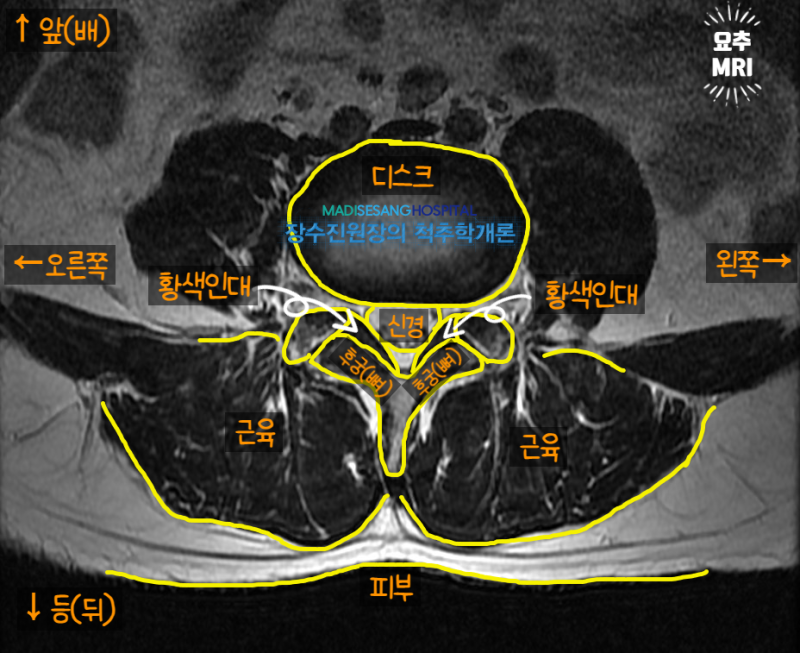

허리관협착증, 목관협착증은 척추의 특정 부위가 좁아지고 신경이 눌려 통증과 불편함이 나타나는 질환이다. 노화는 두 질병 모두의 가장 큰 원인이며, 과체중, 잘못된 자세, 부상 등의 요인도 작용합니다. 그것은 영향을

요추협착증과 경부협착증의 대표적인 증상으로는 통증, 저림, 근육 약화 등이 있습니다. 요추협착증의 경우 허리 통증이 엉덩이, 다리까지 방사될 수 있고, 목협착증의 경우 목, 어깨, 팔까지 통증이 방사될 수 있습니다. .일상 활동이 어려워지고 운동 범위가 제한될 수 있습니다.